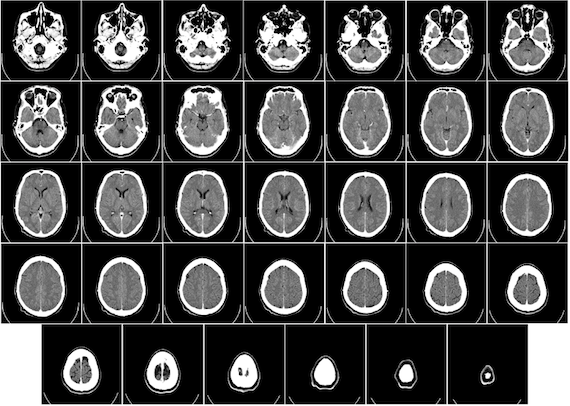

Los especialistas seccionaron el cerebro en más de siete mil 400 láminas, siendo cada sección más delgada que un cabello humano y con un nivel de detalle casi celular, publicó la revista Science.

"Las células están un poco borrosas, pero podemos ver cómo están distribuidas y con qué densidad. Estamos viendo hasta el último rincón del cerebro", dijo Katrin Amunts, profesora de la Universidad de Düsseldorf y directora del proyecto.

Los investigadores descubrieron que las células se reparten según la función cerebral y –dependiendo de si un área determinada sirve para dirigir movimientos o procesar sonidos o estímulos luminosos– las células se distribuyen en ellas.